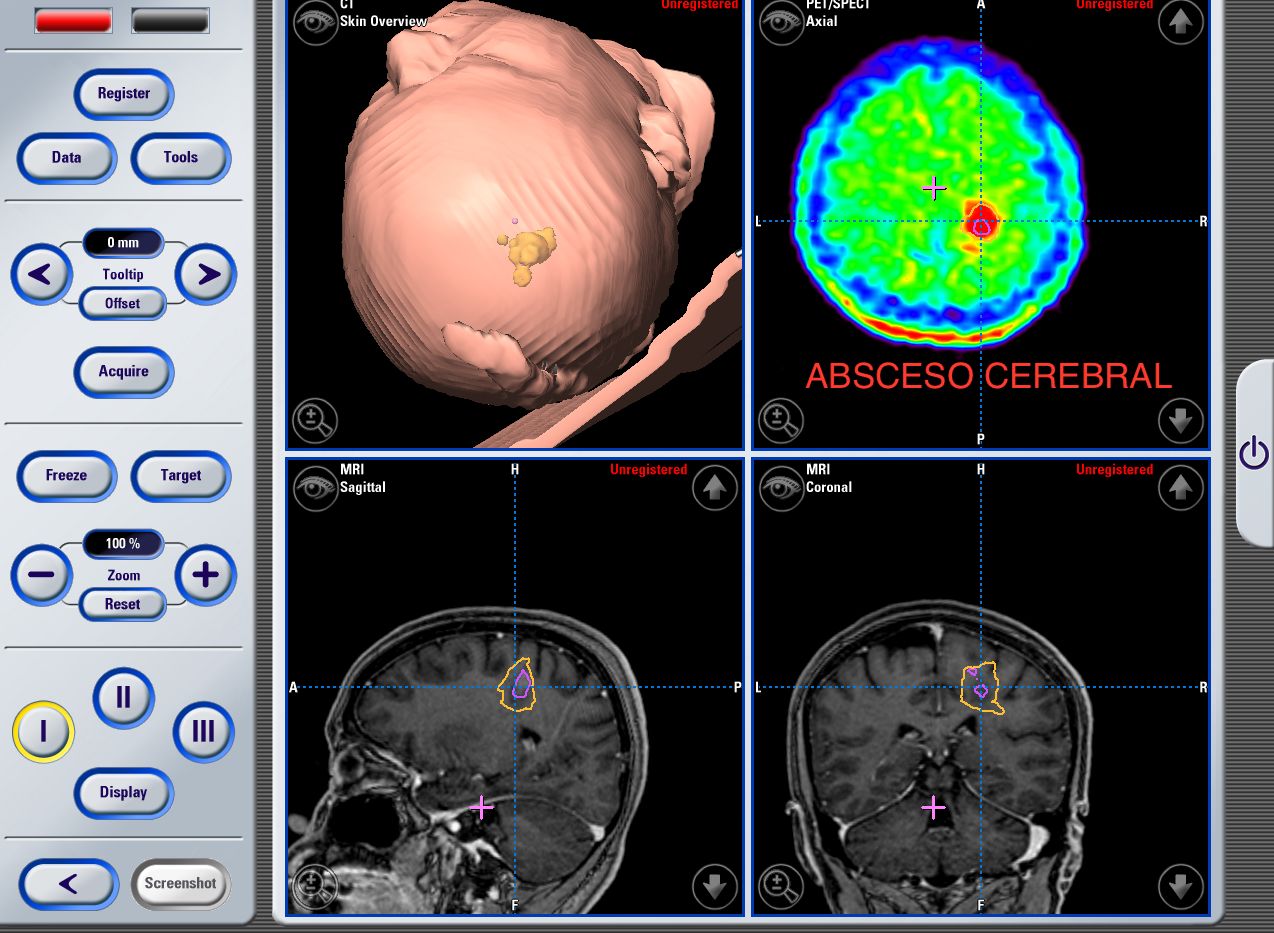

Craniectomia de absceso intracraneal